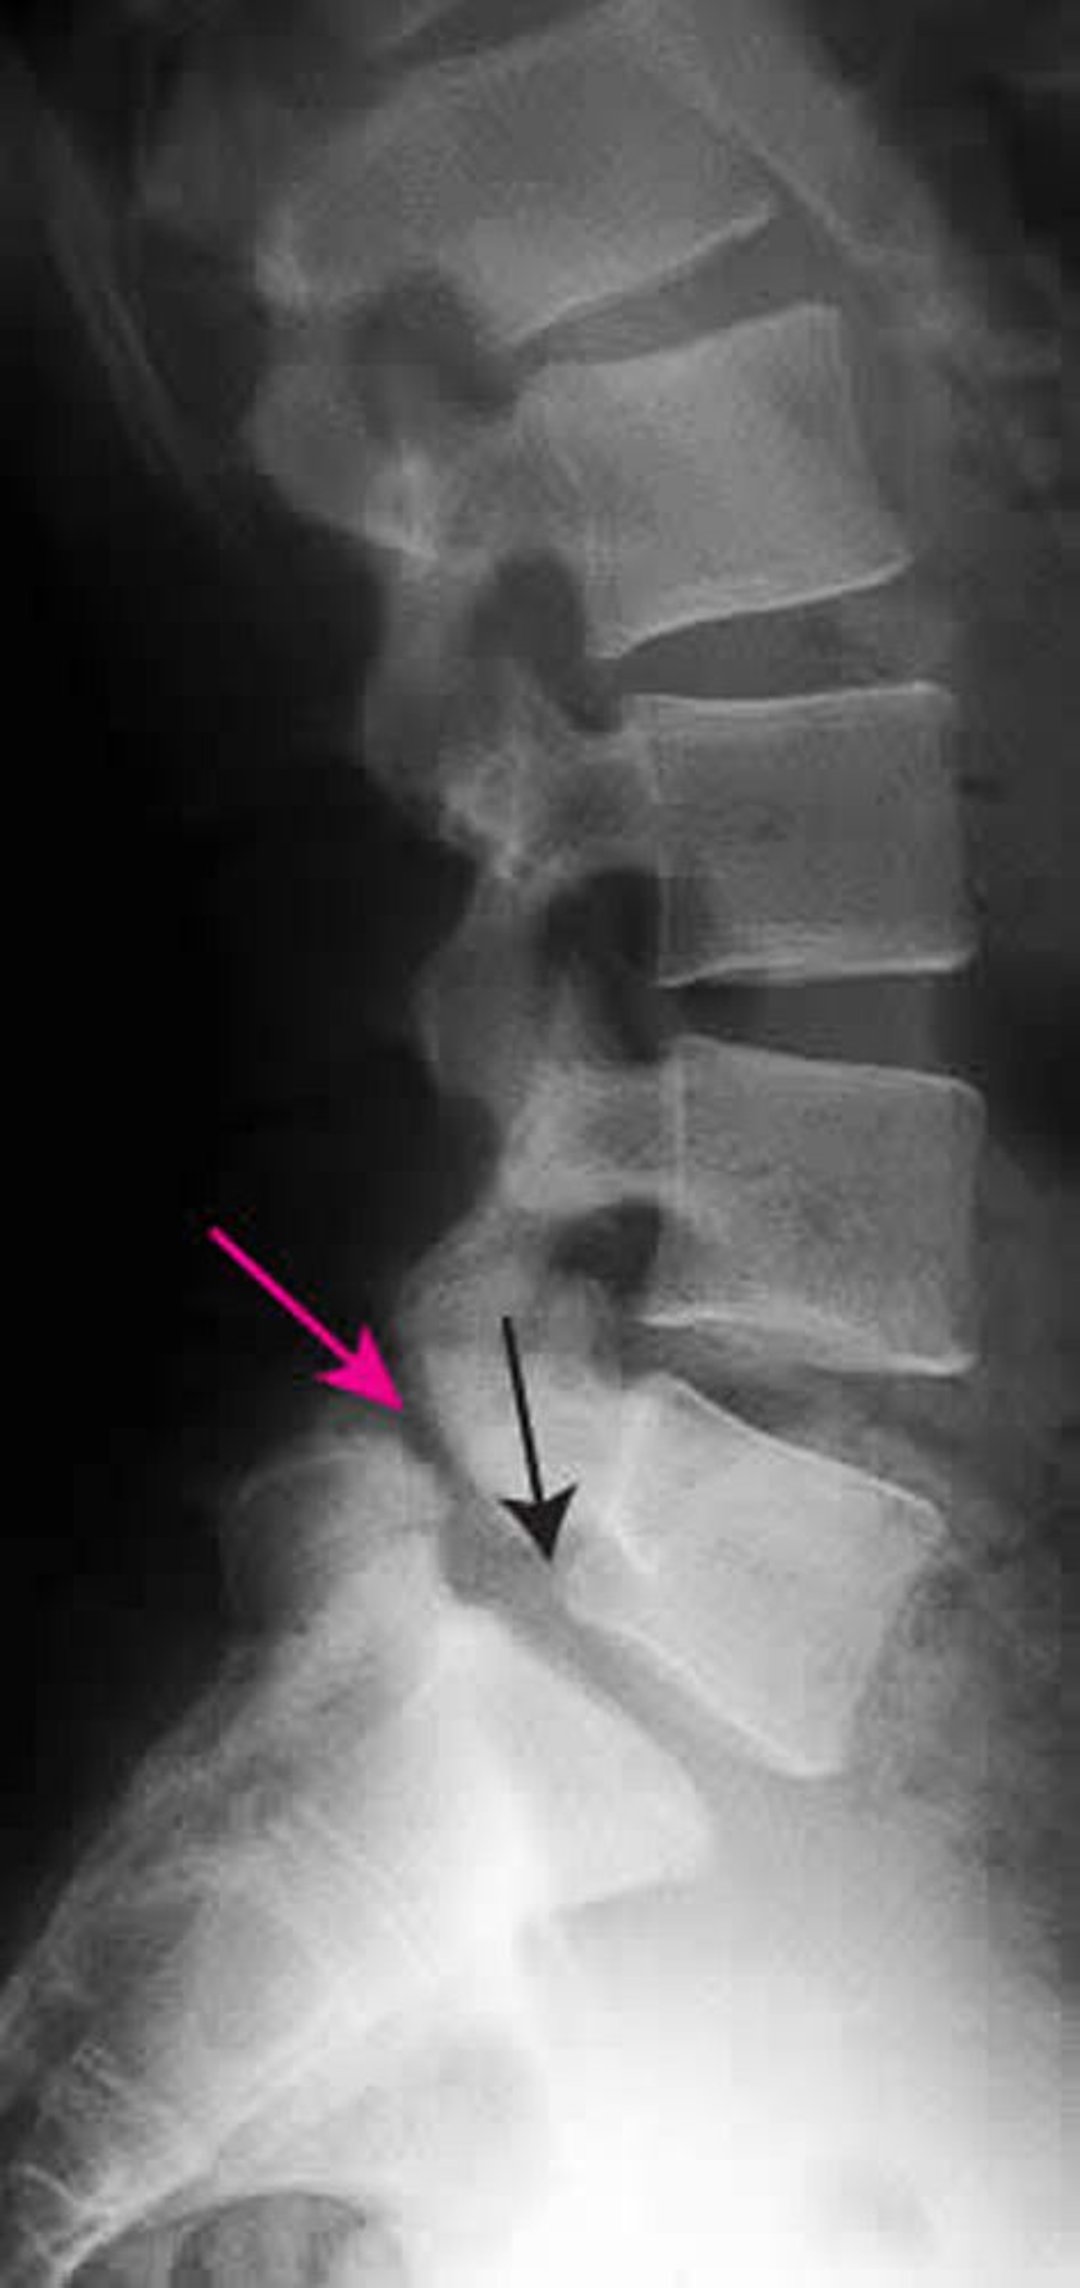

Espondilolistese

Essa radiografia mostra o estágio 1 da espondilolistese da L5 na S1. A seta preta mostra a borda posterior de L5, que tem subluxação anterior a S1. A seta vermelha aponta a espondilólise (defeito congênito na pars interarticularis).

ZEPHYR/SCIENCE PHOTO LIBRARY